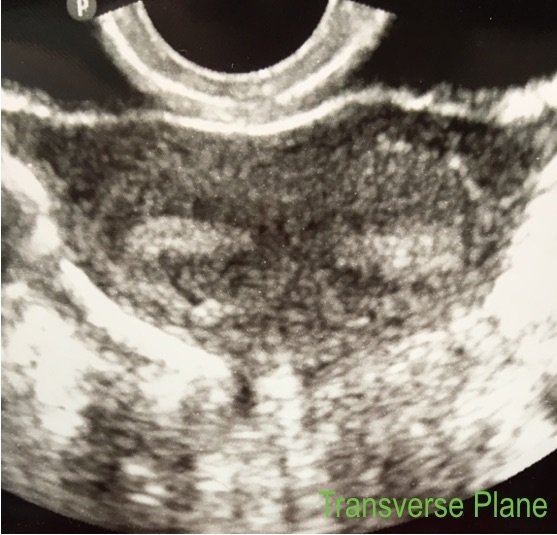

4. Try putting the balloon in the cervix.

Sometimes due to the acuteness of the uterocervical angle, the flexible catheter cannot pass easily into the endometrial cavity. Other times, the views of the cavity are incomplete because the tip of the catheter (and the balloon) are situated in the cornua and the contrast doesn’t distend the rest of the cavity well. Or, sometimes, the cavity won’t distend well because the contrast is leaking of the cervix.

In each of these cases, try this: place the catheter balloon in the cervix rather than the endometrial cavity, near the internal os, and inflate it. This will put the tip of the catheter in the lower uterine segment and the inflated balloon will occlude the cervical canal enough to force the contrast material upwards. This usually works and can make using a painful tenaculum unnecessary (either to pull on and straighten out the uterocervical angle or to try to occlude the cervical canal).